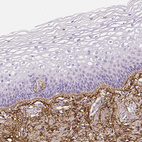

Immunohistochemistry analysis in human cervix, uterine and cerebral cortex tissues using HPA021057 antibody. Corresponding FBN1 RNA-seq data are presented for the same tissues.